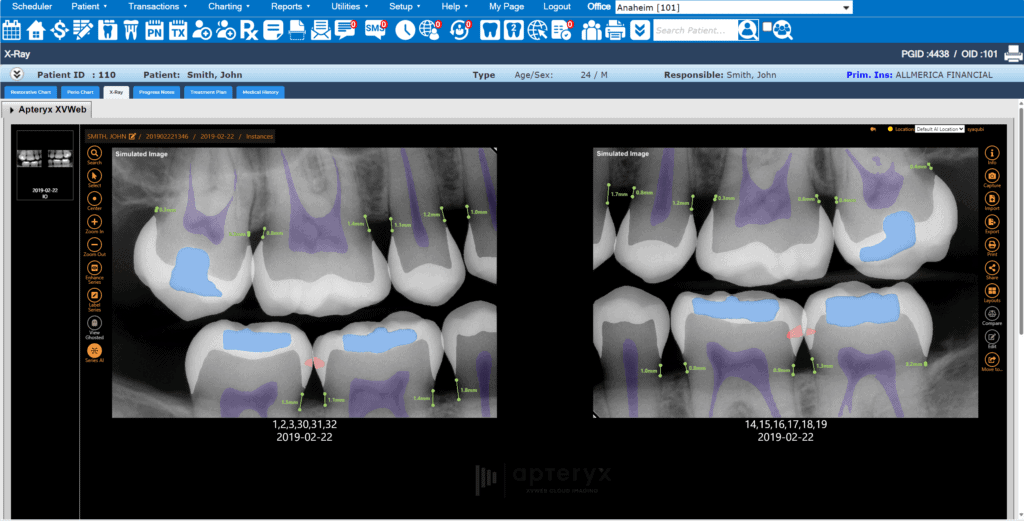

Embedded AI for X-ray Analysis

Leverage advanced AI overlays to improve diagnostic accuracy and consistency for dental professionals and help patients visualize areas of concern. With real-time FDA-cleared AI analysis, share more “a ha” moments with patients to increase case acceptance by up to 30% and submit insurance claims with confidence.

Apteryx XVWeb Dental Imaging is an intuitive cloud-based dental imaging software that allows dentists to capture, view, edit, annotate, and send images securely and easily.

Custom clinical filters and image enhancement tools, templates, bitewings & measurement tools to improve diagnostic accuracy.